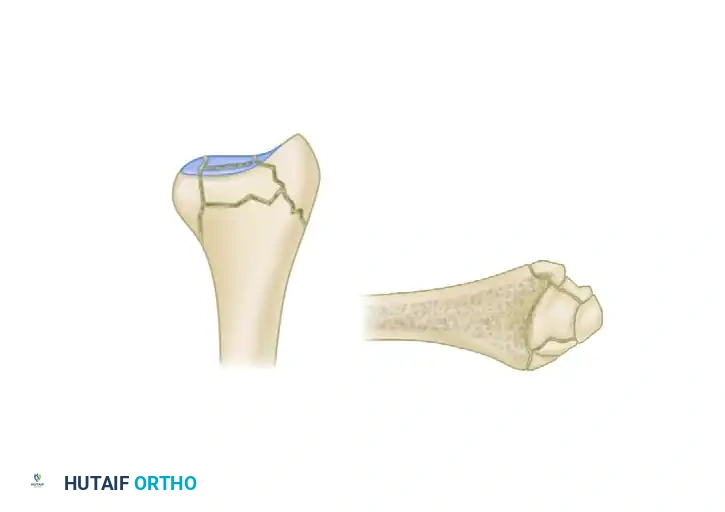

The Five Fracture Fragments

In severe high-energy or osteoporotic distal radius fractures, the bone typically fails in a predictable pattern, resulting in up to five distinct potential fracture fragments:

1. Radial Column (Styloid)

2. Dorsal Cortical Wall

3. Dorsal Ulnar Split

4. Volar Rim (Lunate Facet)

5. Central Intra-articular Fragment

Thin metaphyseal cortical bone does not hold standard screws well. Furthermore, conventional thick plates cannot be applied easily to the dorsal aspect of the distal radius due to the high risk of extensor tendon irritation and eventual rupture. Fragment-specific fixation utilizes low-profile wire-forms and pin-plates to capture these specific fragments without adding excessive bulk.

Associated Surgical & Radiographic Imaging